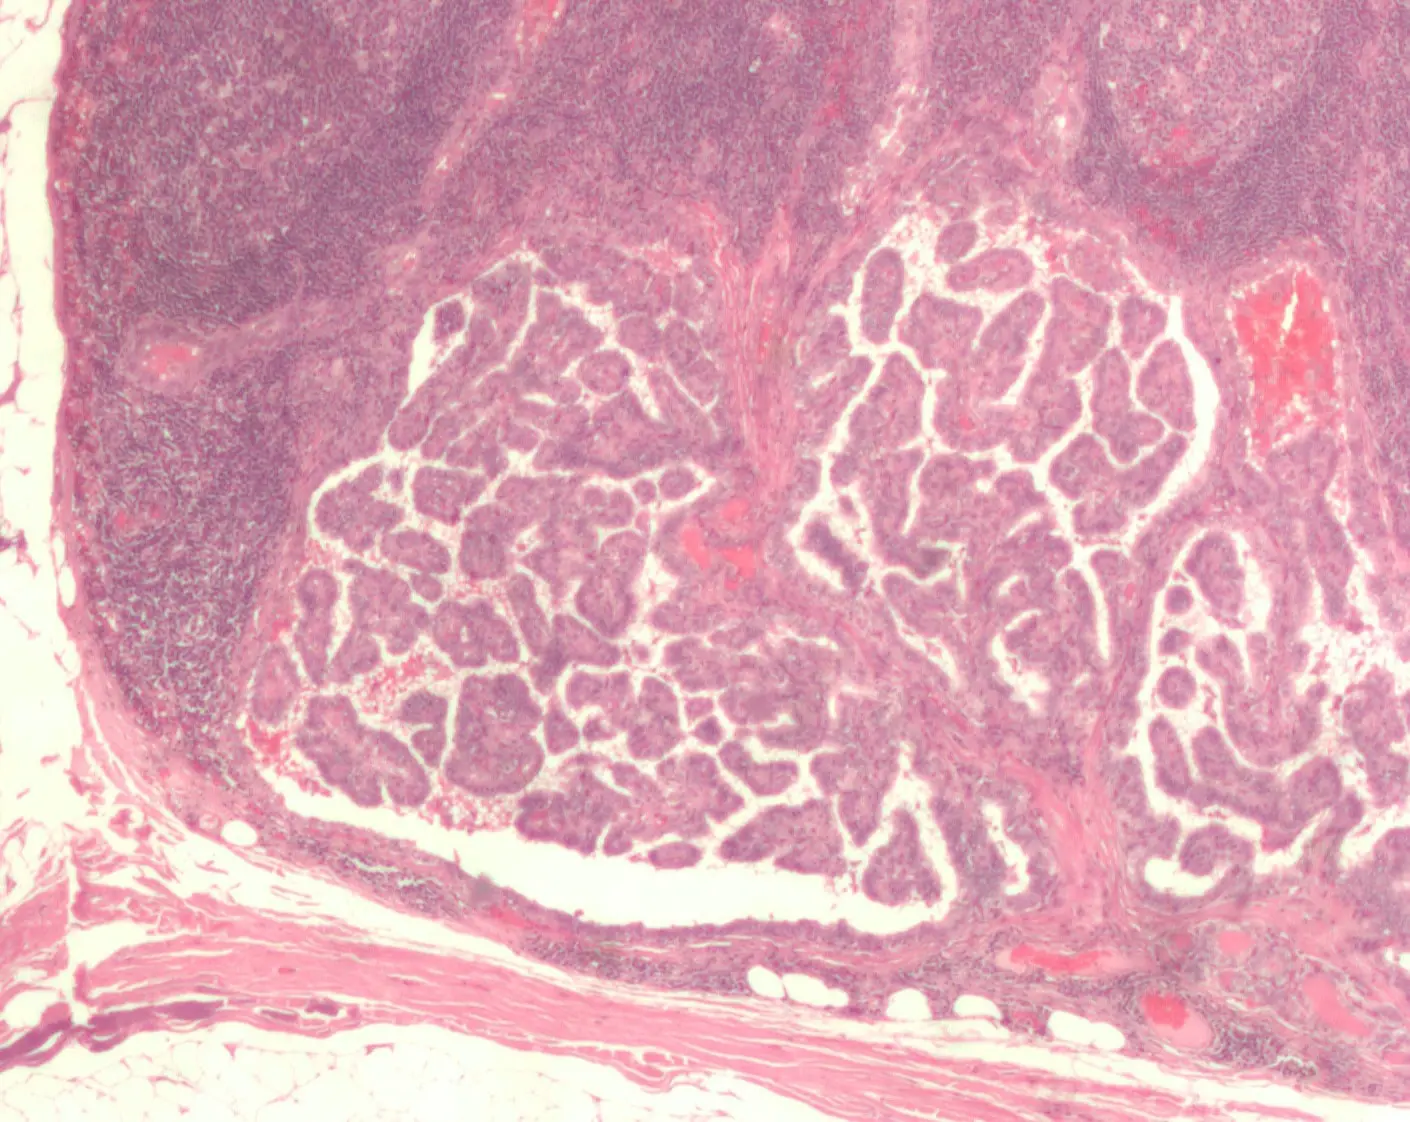

Рак — это результат нарушенной работы клеток, когда одна или несколько из них «забывают» привычный жизненный цикл: созревание, выполнение функций и своевременную смерть. Отклонения в этом процессе оборачиваются бесконтрольным размножением, из-за чего формируется опухоль. Она способна внедряться в соседние здоровые ткани, а также распространять клонированные клетки по всему организму через кровь и лимфу, формируя вторичные очаги — метастазы.

Новая модель помогла выявить интересную тенденцию: у пожилых людей среди всех онкологических заболеваний на лидирующие позиции выходят не самые часто обсуждаемые виды рака, а те, которые отличаются высокой смертностью, но менее известны широкой публике. Например, злокачественные образования органов пищеварения становятся ключевым возрастозависимым видом: их доля достигает почти трети (31,9%) в общем объеме риска у 70-летних, а шанс заболеть этой формой рака у людей старшего возраста увеличивается в 168 раз по сравнению с 20-летними.

Профессор Трусов отмечает: «Наш анализ показал, что именно опухоли пищеварительной системы играют определяющую роль в возрасте, в то время как такие распространенные заболевания, как рак молочной железы, существенно теряют значимость для старших возрастов. Доля этого диагноза уменьшается с 40,4% у молодежи до всего 6,3% после 70 лет». Это свидетельствует о том, что у рака молочной железы возраст не столь критичен, а решающими оказываются иные причины — наследственность и влияние окружающей среды.